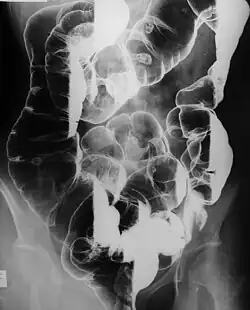

Peutz–Jeghers syndrome (often abbreviated PJS) is an autosomal dominant genetic disorder characterized by the development of benign hamartomatous polyps in the gastrointestinal tract and hyperpigmented macules on the lips and oral mucosa (melanosis).[2] This syndrome can be classed as one of various hereditary intestinal polyposis syndromes[3] and one of various hamartomatous polyposis syndromes.[4] It has an incidence of approximately 1 in 25,000 to 300,000 births.[5]

- Hamartomatous polyps in the gastrointestinal tract. These are benign polyps with an extraordinarily low potential for malignancy.